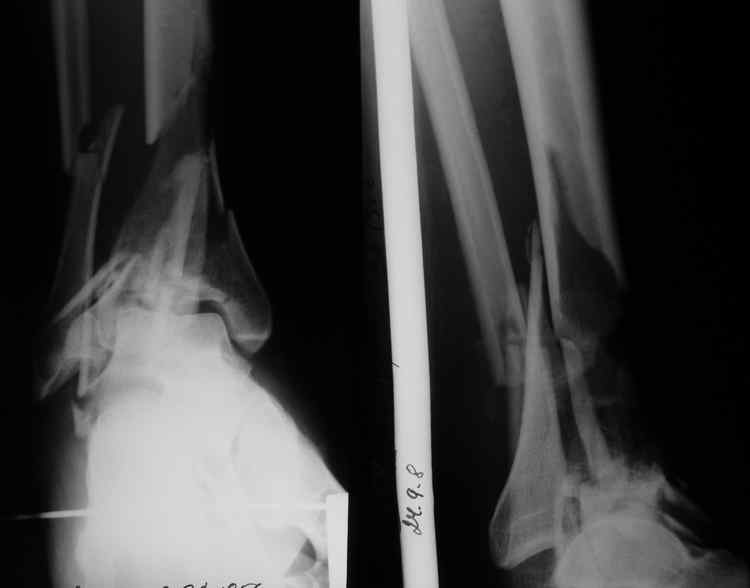

Re: Тяжелый перелом пилона

Alexander Chelnokov 01 Октябрь 2008, 11:07

Первым этапом наложить бы дистрактор "голень-стопа". После улучшения состояния мягких тканей - открытая репозиция в первую очередь суставной поверхности, с фиксацией либо аппаратом, либо пластиной. Это если коротко и в общем. Если интересуют какие-то частности - давайте их обозначим и обсудим.